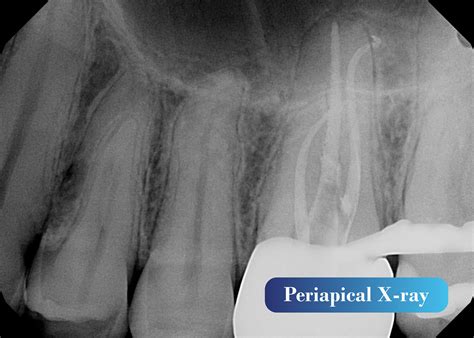

When you visit your dentist for a toothache or a routine check-up, they may recommend a specific type of dental imaging to get a clearer picture of your oral health. Among the various diagnostic tools available in modern dentistry, the Periapical X Ray stands out as an essential imaging technique. Unlike broader panoramic X-rays that capture the entire jaw, a periapical image focuses on one or two specific teeth, providing an incredibly detailed view of the tooth from the crown down to the very tip of the root and the surrounding bone structure. Understanding what this procedure entails can help alleviate any anxiety you might feel about your upcoming dental appointment.

A Periapical X Ray, often referred to simply as a "PA," is a close-up, high-resolution diagnostic image. The term "periapical" literally translates to "around the apex," with the apex being the tip of the tooth root. This specific type of X-ray is designed to show the entirety of the tooth—from the biting surface (crown) down to the root end—as well as the surrounding supporting bone.

Because it offers such fine detail, dentists utilize this scan to diagnose specific problems that might be missed by broader imaging methods. Whether you are experiencing localized pain, sensitivity, or require a procedure that demands precision, this X-ray is often the first step toward an accurate diagnosis.

• Root Canal Planning: To visualize the shape, length, and condition of the root canals before performing a root canal treatment.